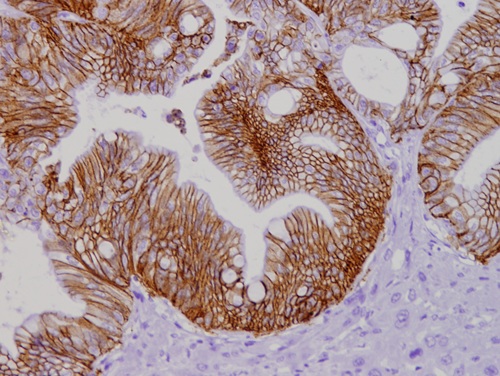

Metàstasi tenyida amb l'anticòs contra CDH17

Alvarez-Villanueva D, Maqueda M, Harti D, Canton E, Andrades E, Bertran J, Martínez-Iniesta M, Solé L, García-Hernández V, Montoto Á, Lobo-Jarne T, Alonso-Marañón J, Herrero-Molinero P, Larrubia-Loring M, Tramuns A, Wynne K, Bera I, Matallanas D, Villanueva A, Bigas A, Iglesias M, Espinosa L. Tight junction-high and CDH17-positive cell population is the source of colorectal cancer liver metastases. Nat Commun. 2026 Jan 3;17(1):1425. doi: 10.1038/s41467-025-68169-3. PMID: 41484106; PMCID: PMC12881549.